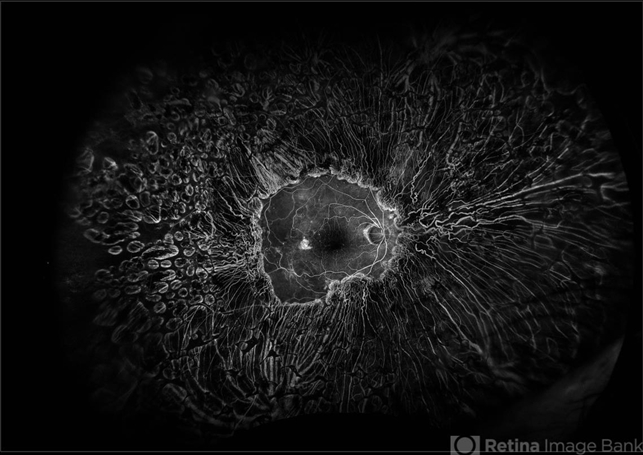

- pan-retinal photocoagulation (PRP)

Fundus camera

OPTOS - Description

- Diabetic retina treated with complete 360 PRP laser, taken during fluorescein angiogram.